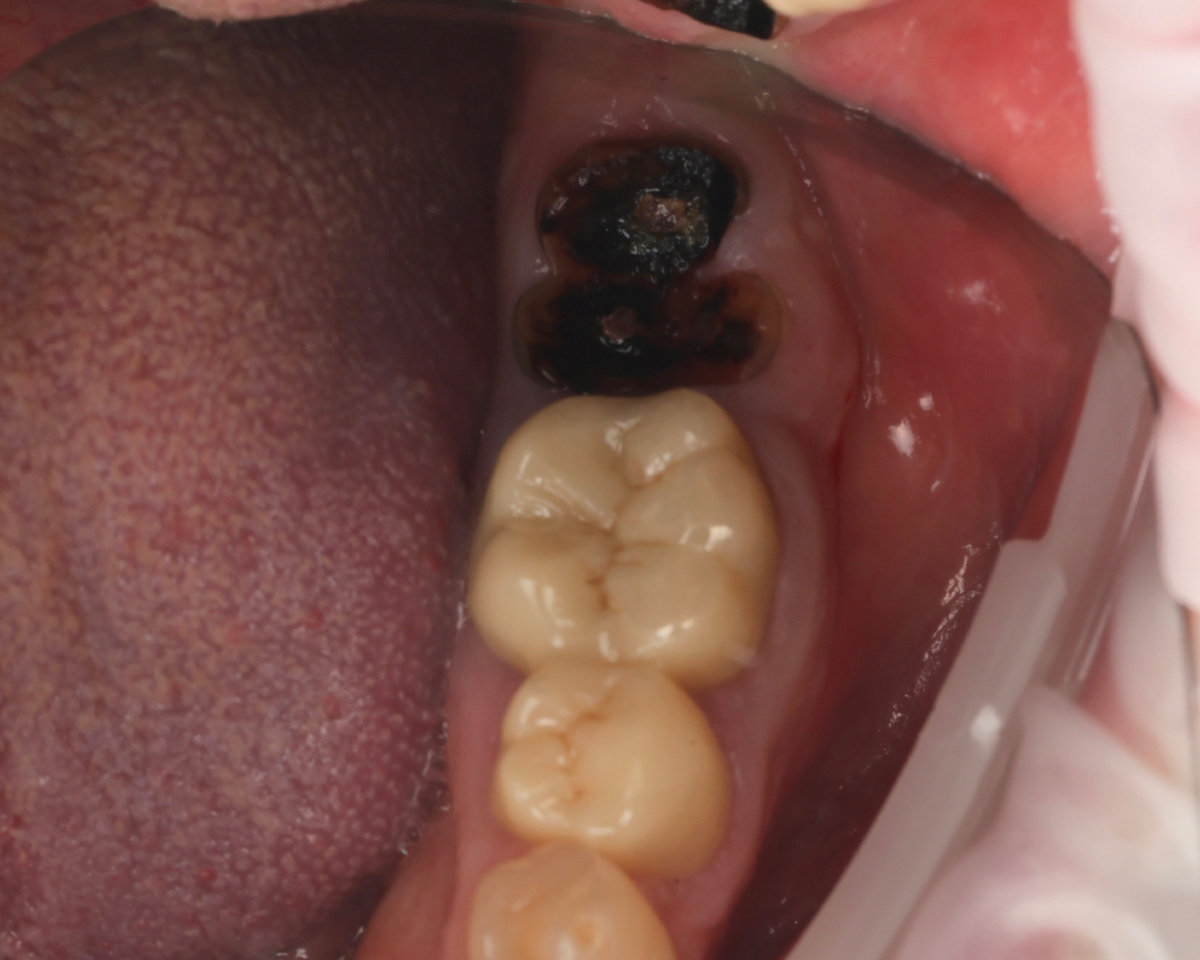

От этого зуба остались только ножки... Без рожек. Корни разошлись в разные стороны, коронковая часть сгнила. Торчат из десны 2 чёрных кариозных "глазёнка" (чуть позже покажу во всей красе).

Пациент пришёл с зубом 3.7 (нижняя челюсть, жевательная группа), от которого остались лишь гнилые корешки:

-2

И ведь посмотрите на качество эндодонтии - всё хорошо. На верхушках корней нет какого-то ужасающего воспаления. Эх... Жил бы да жил зуб, если бы коронковая часть была сохранна. Но коронковая часть отвалилась. Честно - не спрашивала, почем так произошло. Не подскажу причину.

Что с таким зубом делать? Ничего. Даже наши крутейшие волшебные терапевты не спасут подобное. И никто не спасёт, как бы ни обещали обратное. Ненадёжно. Поезд ушёл.